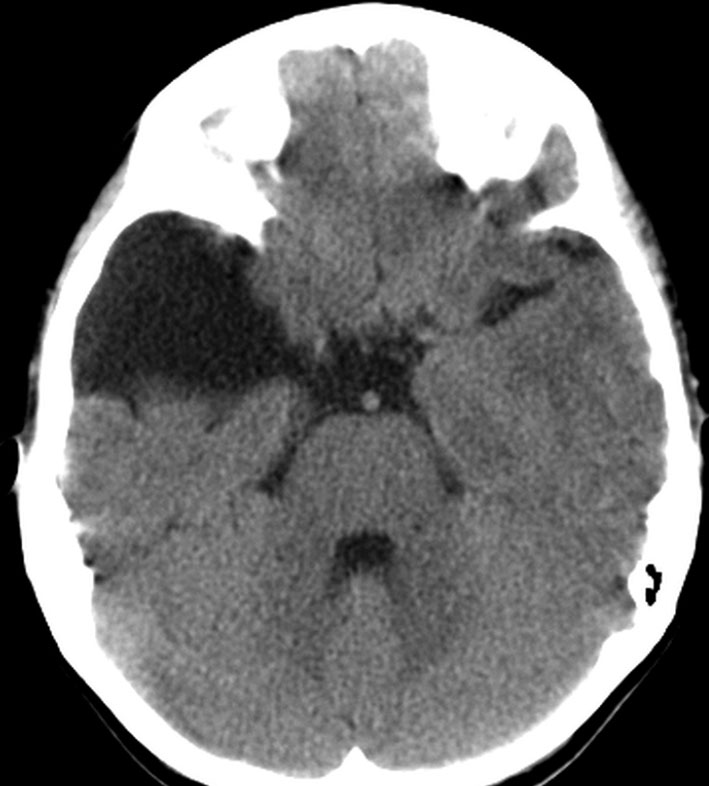

シルビウス裂くも膜のう胞,中頭蓋窩くも膜のう胞

最も多いタイプで50%くらいです。7歳の子に偶然発見された右シルビウス裂のくも膜のう胞です。大きいのですがこの程度では治療の必要はありません。シルビウス裂のくも膜のう胞は最も多いものです。

前の例より少し大きいものです。1歳4ヶ月までは,のう胞が増大しましたがその後は同じ大きさで経過しました。